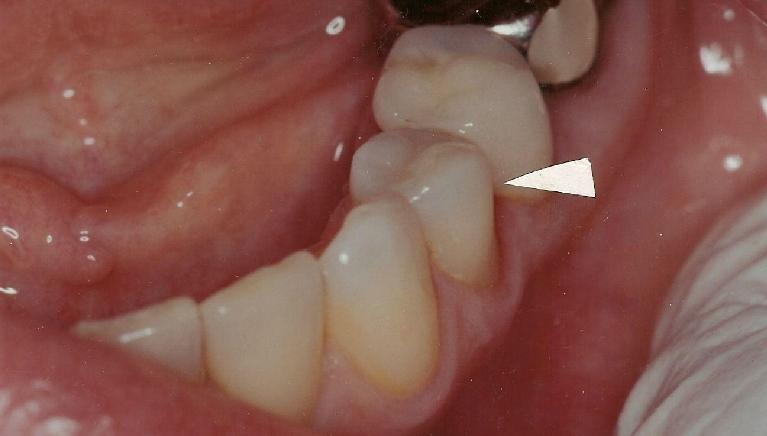

Before

Repair of fractured incisor with composite resin.

This young Yale student fractured her two front teeth a few days after arriving in New Haven to begin her graduate school. She had recently bleached her lower teeth before leaving home.

Composite resin was bonded to the fractured area, and her treatment was completed within an hour.